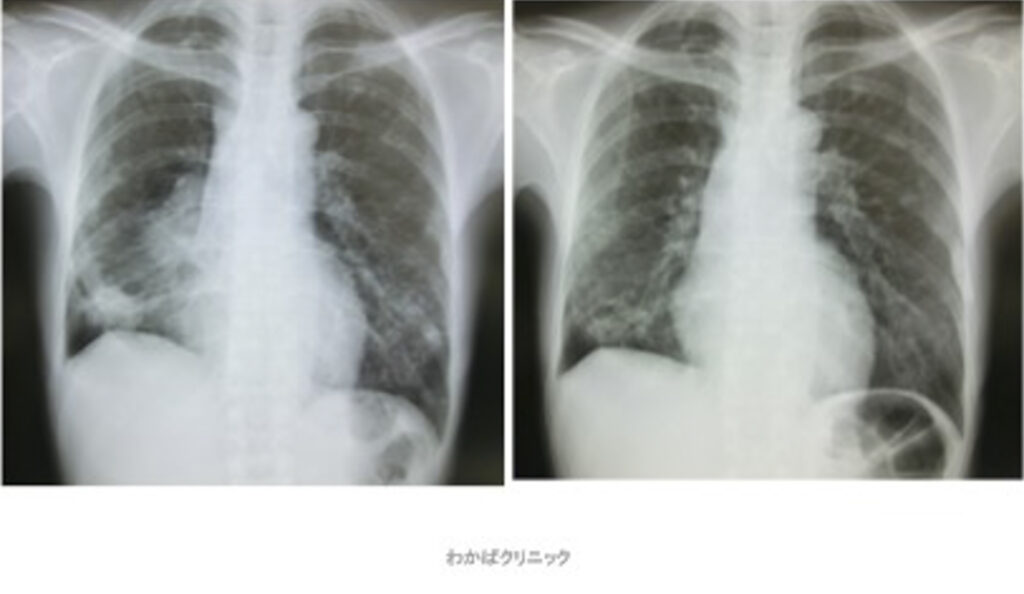

- 西洋医学的な効果判定(必ず必要です)

- CT・MRI・超音波検査 他